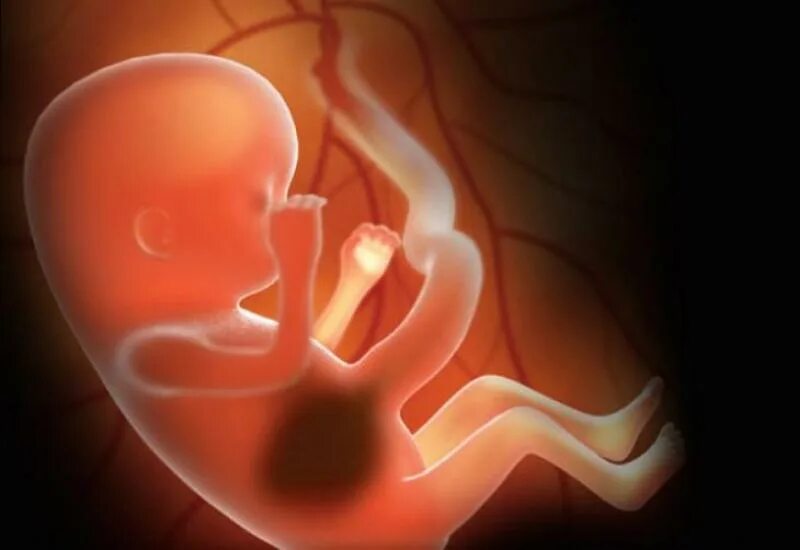

Ребенок в 13 недель